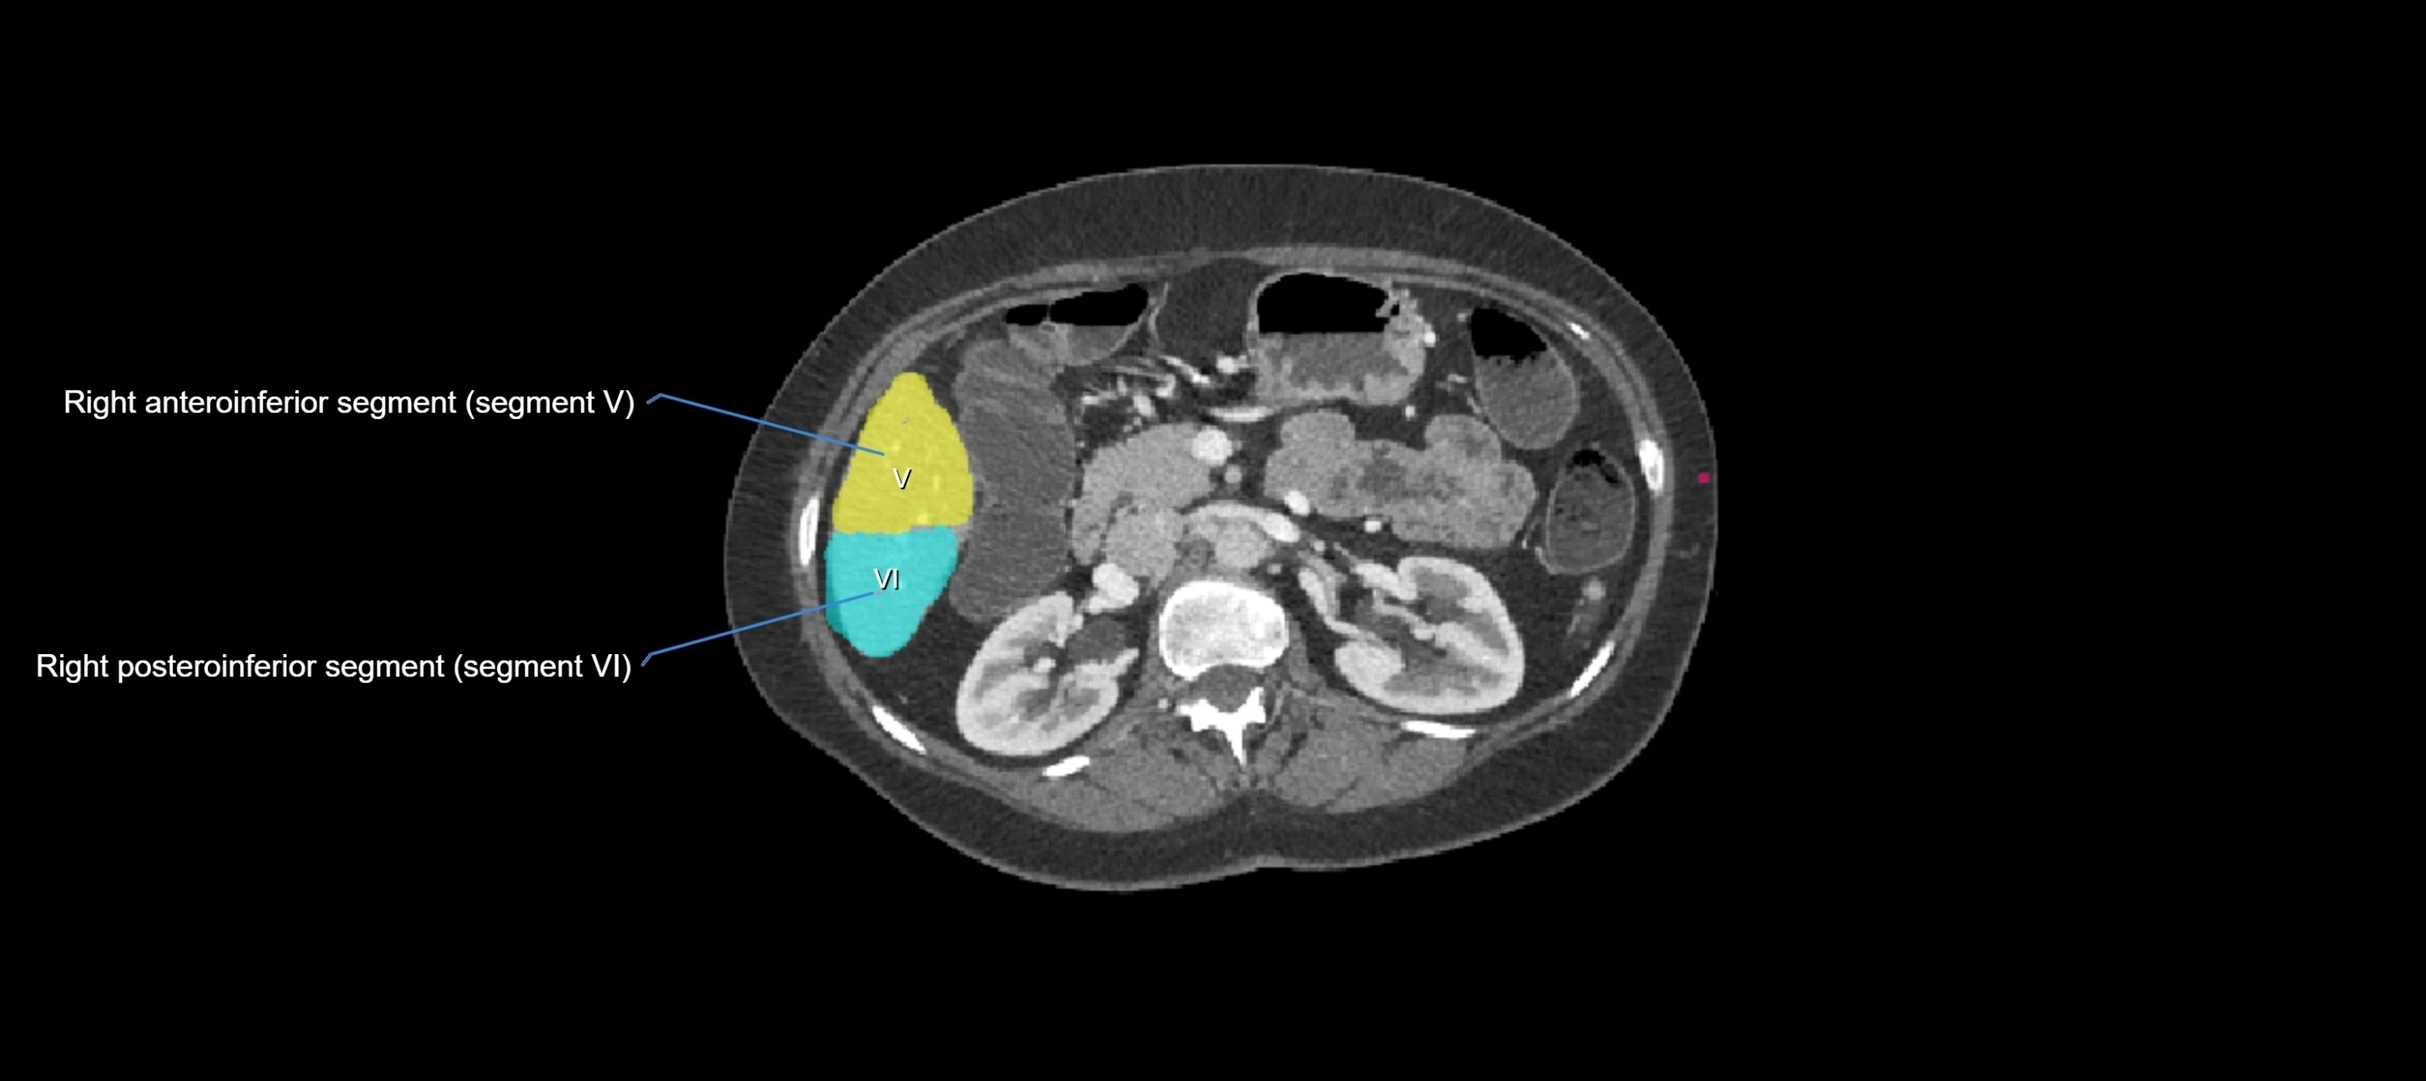

CT Image

image